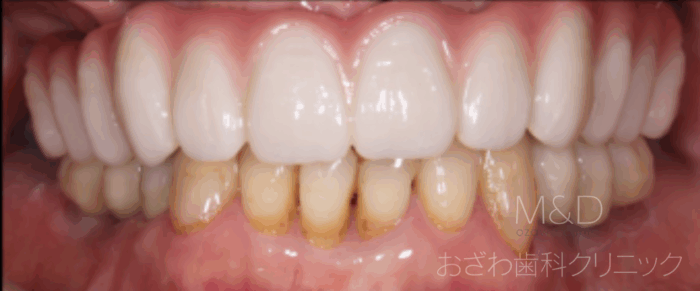

術後

オールオン症例

上顎 450万円(税別)、下顎 200万円 計 650万円(税別